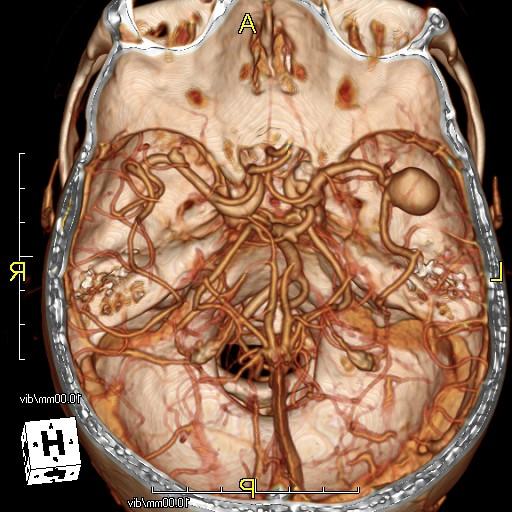

Túi phình động mạch não giữa bên trái (mũi tên đỏ) trên hình chụp CT mạch máu não và hình chụp mạch máu não thông thường của bệnh nhân bị xuất huyết dưới nhện.

Hình chụp CT mạch máu não của bệnh nhân bị xuất huyết dưới nhện do có túi phình động mạch thông trước (mũi tên đỏ).